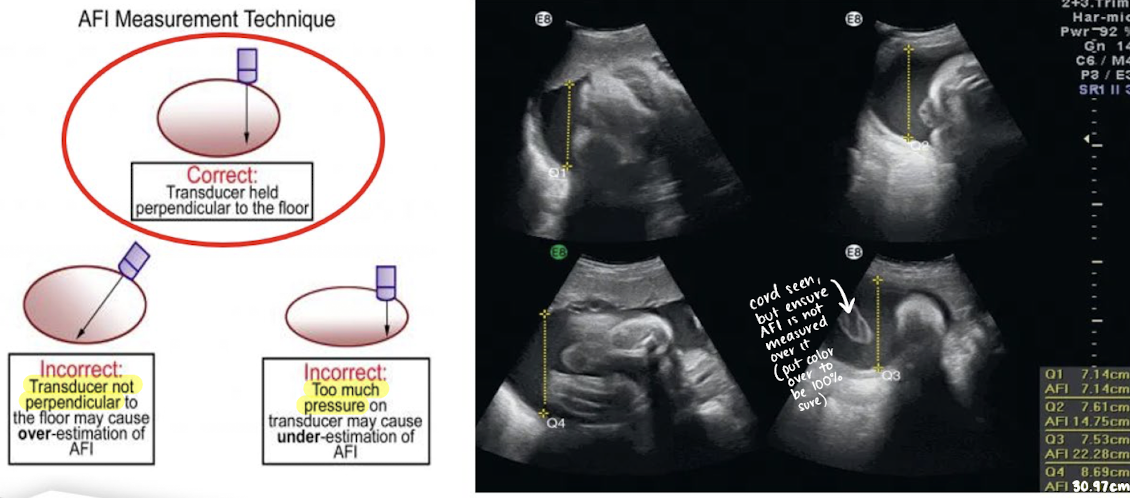

AF measurement method: amniotic fluid index (AFI)

most used method for quantifying amniotic fluid volume

uterine cavity is divided into 4 equal quadrants

largest pocket in each quadrant is measured (AP) in SAG plane and added together

transducer should be perpendicular to table, not curved skin surface

exclude fetal limbs and umbilical cord loops )can use color Doppler)

do NOT measure through a structure

AF measurement method: AFI example

normal AFI values

10 cm < AFI < 20 cm

should be between 10-20 cm

borderline AFI values

5-10 cm (low side); 20-24 cm (high side)

abnormal AFI values

oligohydramnios (too little)

AFI < 5 cm

polyhydramnios (too much)

AFI > 24 cm